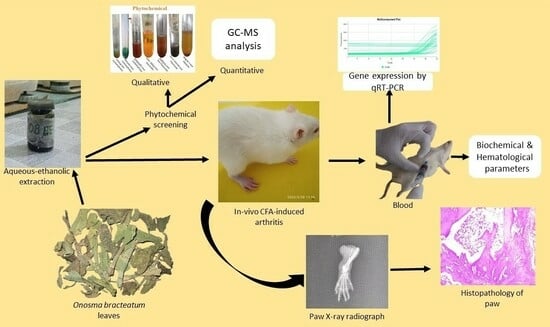

Onosma bracteatum Wall Aqueous–Ethanolic Extract Suppresses Complete Freund’s Adjuvant-Induced Arthritis in Rats via Regulation of TNF-α, IL-6, and C-Reactive Protein

Abstract

:1. Introduction

2. Results

4. Material and Methods

4.3. Plant Assortment

Method for Forming an Aqueous–Ethanolic Extract

4.4. Screening of Phytochemical

4.5. Estimation of Gas Chromatography–Mass Spectrometry (GC-MC)

4.7.4. Complete Freund’s Adjuvant-Induced Arthritis Model